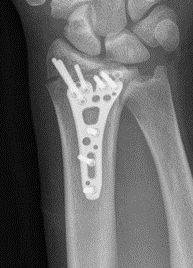

Fracture dislocations

Fragment specific fixation of fractures

Bridging plates

+/- ligament repair

Bridge plate

- distal to index / middle metacarpal

- slide under 2nd extensor compartment (ECRL / ECRB)

- proximal to radius between brachioradialis and ECRL / ECRB

- leave for 10 - 12 weeks

Radial styloid

- percutaneus screws +/- radial styloid plate